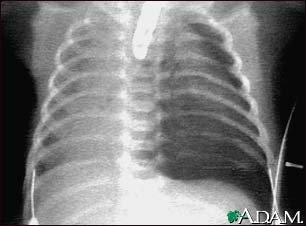

Pneumothorax - chest X-ray

Pneumothorax occurs when air leaks from inside of the lung to the space between the lung and the chest wall. The lung then collapses. The dark side of the chest (right side of the picture) is filled with air that is outside of the lung tissue.